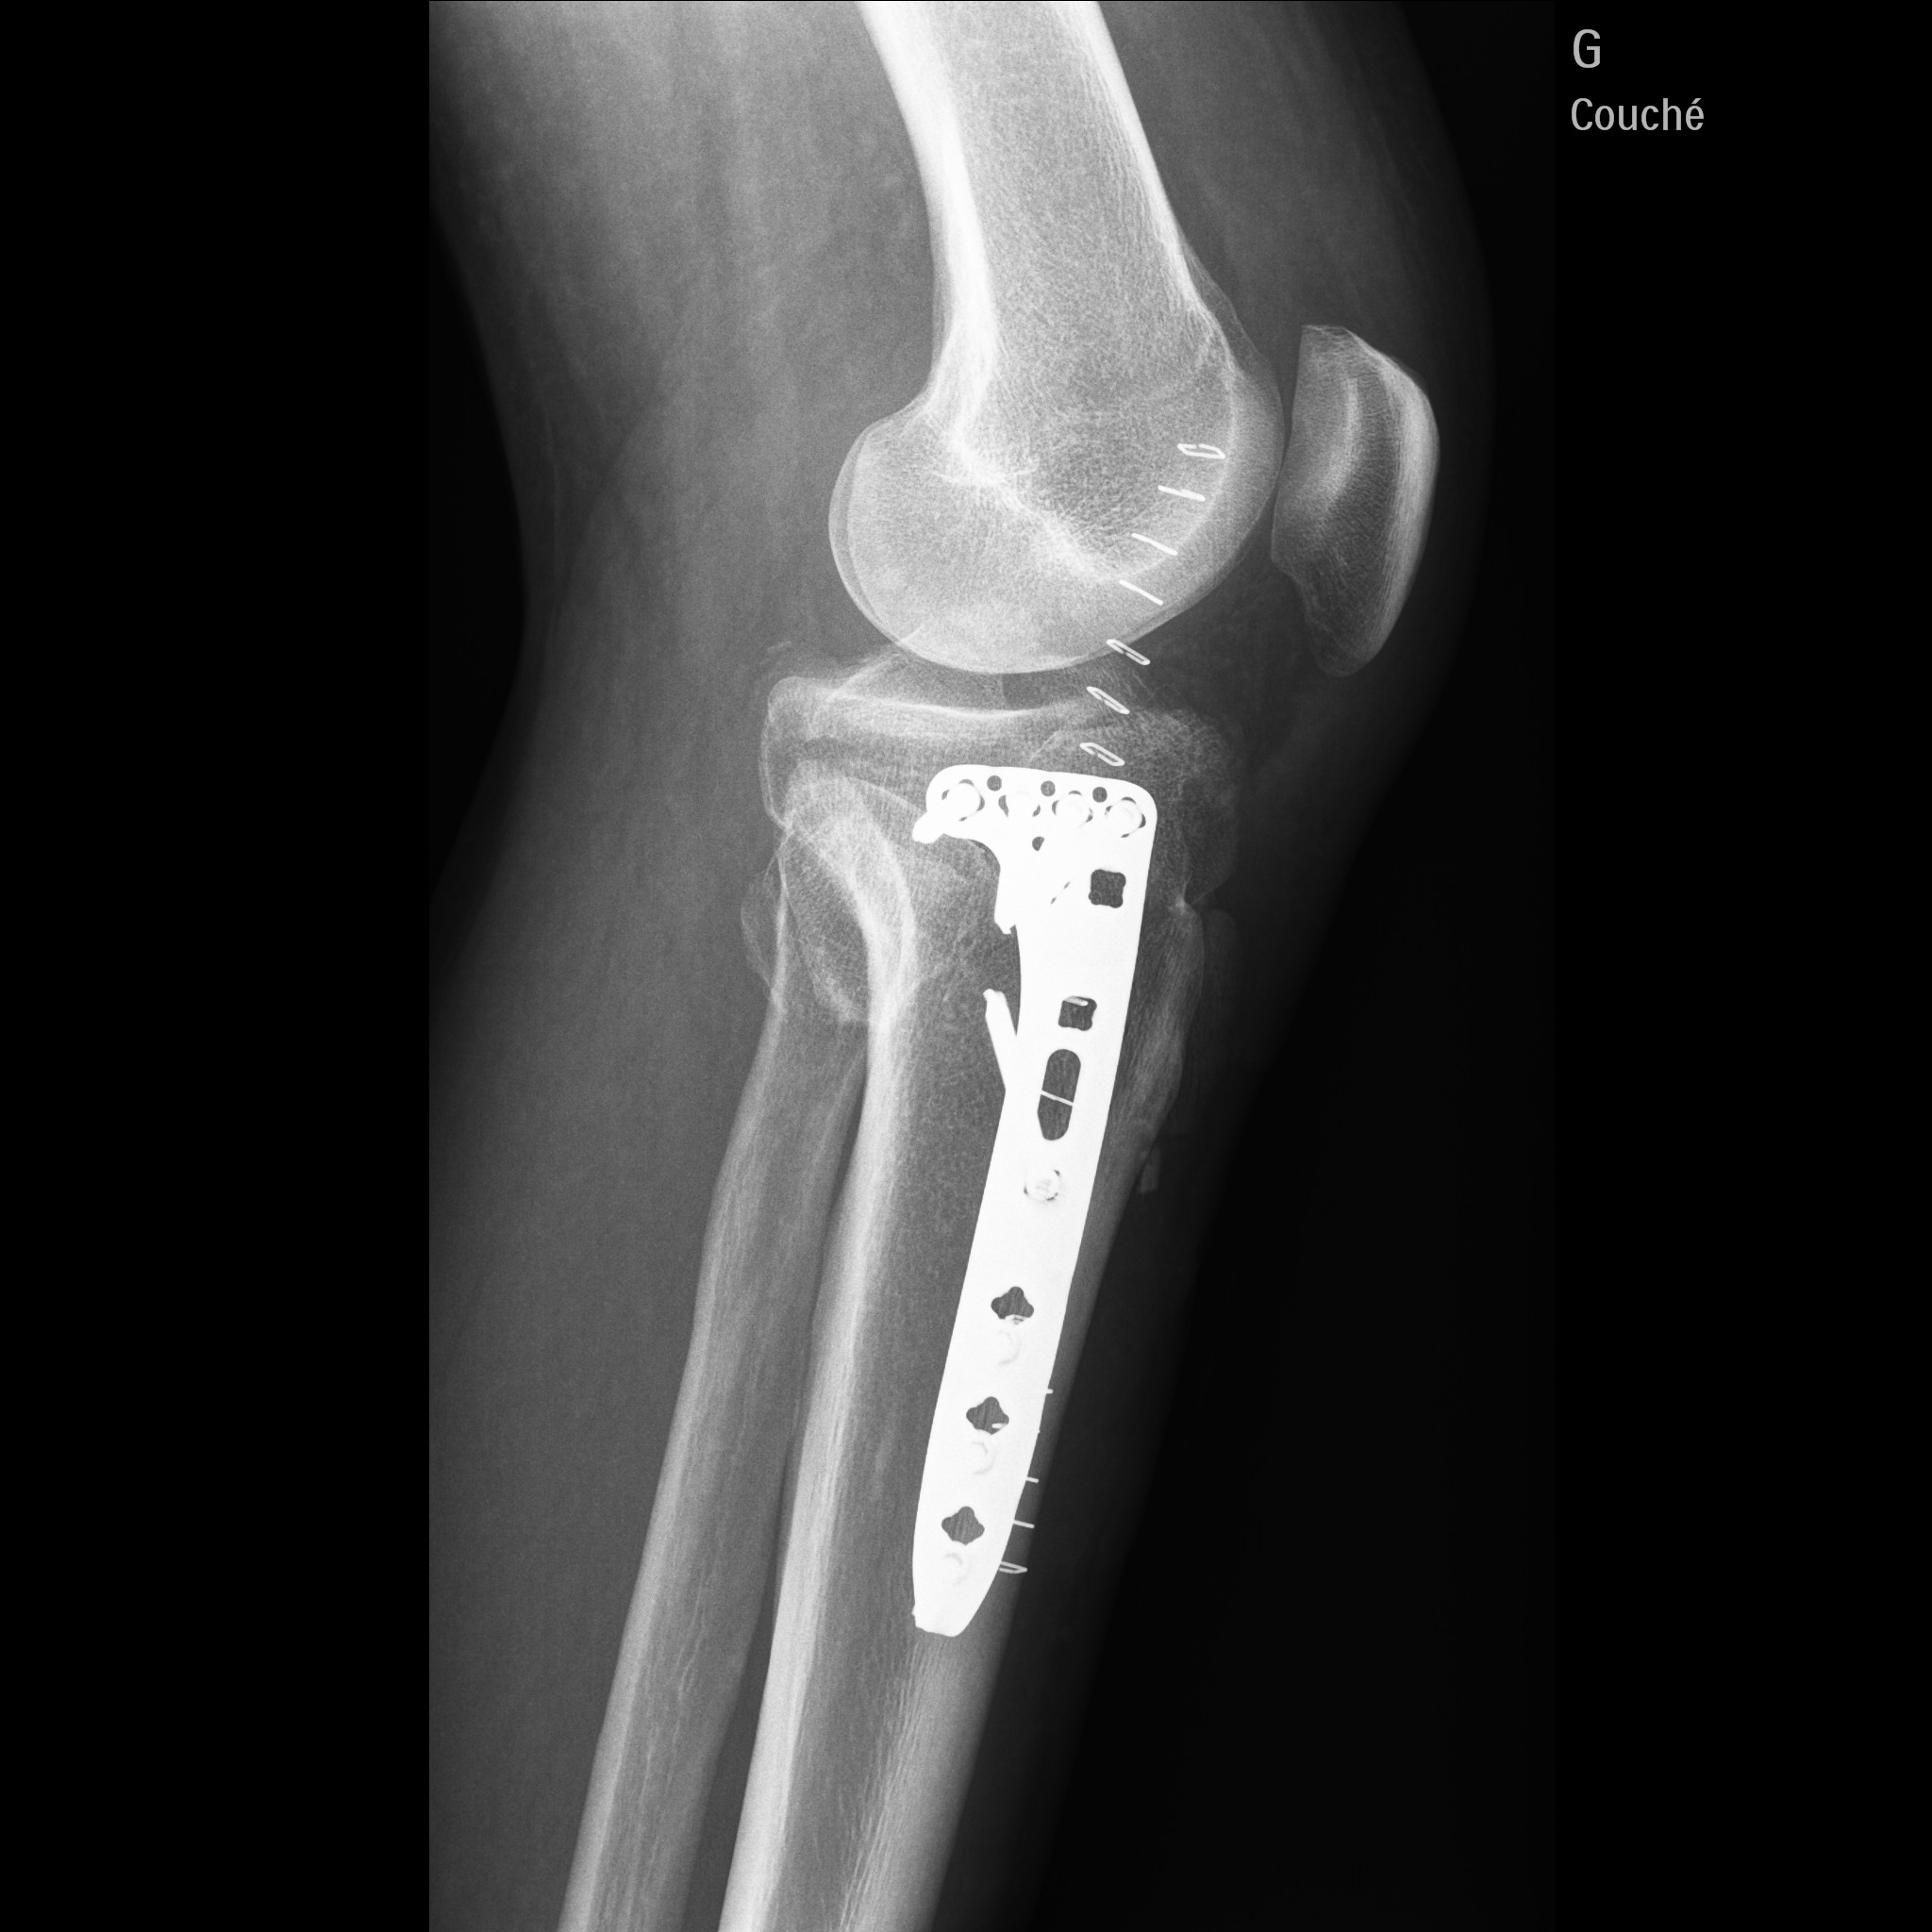

j'ai fait une sale chute en moto et j'ai du me faire opéré :( :( :( :(

j'en ai pour 3 mois sans pauser le pied a terre , et 6 mois de rééducation 1 an pour récupéré la totalité de ma jambes

1.3.46.670589.30.39.0.1.622692733605.1619697890621.1-f1.jpeg

1.3.46.670589.30.39.0.1.622692733605.1619697890648.1-f1.jpeg

Tu as dû avoir la trouille de ta vie. Un peu plus haut c'était toute l'articulation qui prenait.

Ouaouuu....ah oui c est du lourd la. Beau travail de chirurgie...a la hauteur de ce que tu sais faire de ton cote :wink: